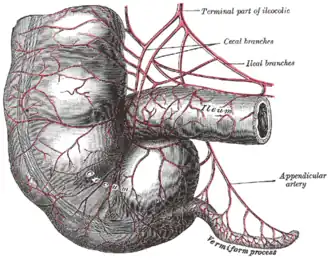

The vermiform appendix is typically used in the Malone antegrade continence enema. | |

The operation involves connecting the appendix to the abdominal wall and fashioning a valve mechanism that allows catheterization of the appendix, but avoids leakage of stool through it. By using the patient’s own appendix for the procedure, doctors can avoid using artificial devices which can be seen and can cause the patient irritation.[1] If the appendix was previously removed or is unusable, a neoappendix can be created with a cecal flap.[2]